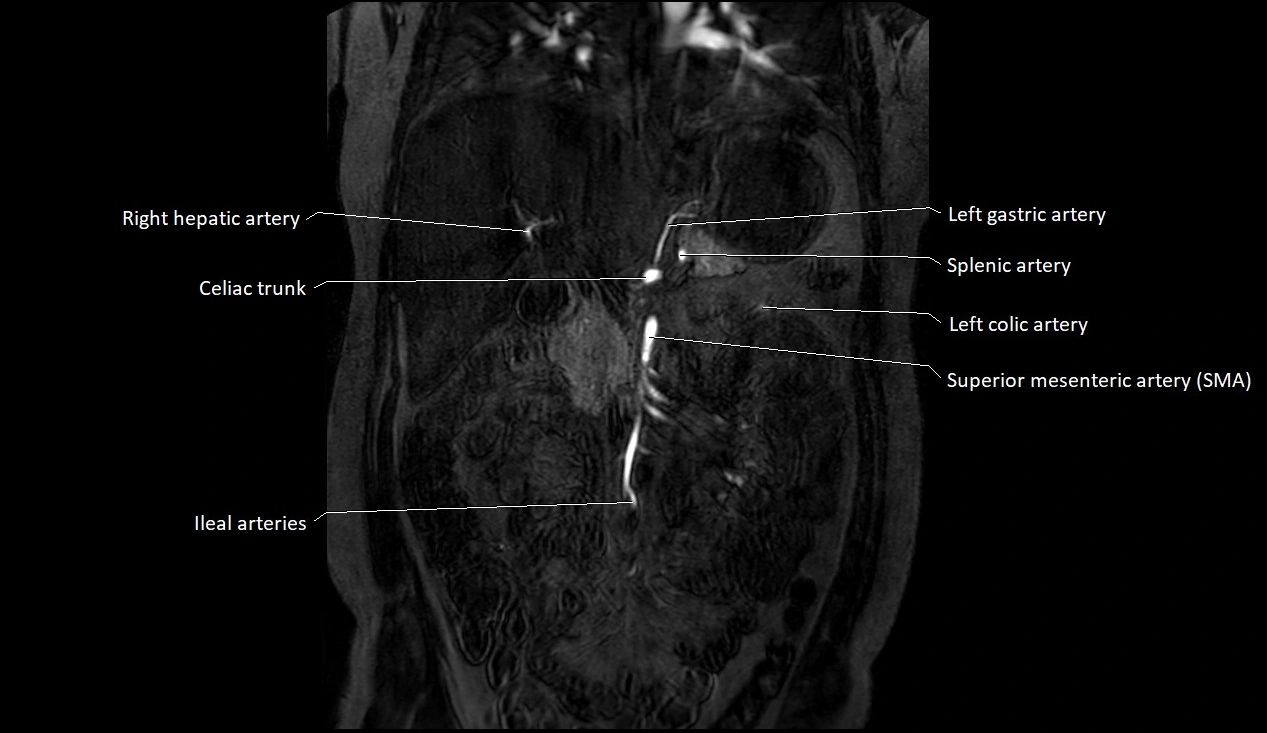

MRA (Magnetic Resonance Angiography):

• Contrast-enhanced MRA provides high-resolution imaging of the aorta and its branches

• Allows 3D reconstruction of visceral, parietal, and terminal branches

• Excellent for evaluating aneurysm size, dissection flap, stenosis, or preoperative planning

• Non-invasive alternative to conventional angiography

MRI images

image